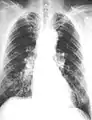

The abnormal chest x-ray and its interpretation remain the most important factors in establishing the presence of pulmonary fibrosis.[11] The findings usually appear as small, irregular parenchymal opacities, primarily in the lung bases. Using the ILO Classification system, "s", "t", and/or "u" opacities predominate. CT or high-resolution CT (HRCT) are more sensitive than plain radiography at detecting pulmonary fibrosis (as well as any underlying pleural changes). More than 50% of people affected with asbestosis develop plaques in the parietal pleura, the space between the chest wall and lungs. Once apparent, the radiographic findings in asbestosis may slowly progress or remain static, even in the absence of further asbestos exposure.[23] Rapid progression suggests an alternative diagnosis.

Severe pleural fibrosis with focal calcification.

61 yr old working industrially with asbestos for decades.